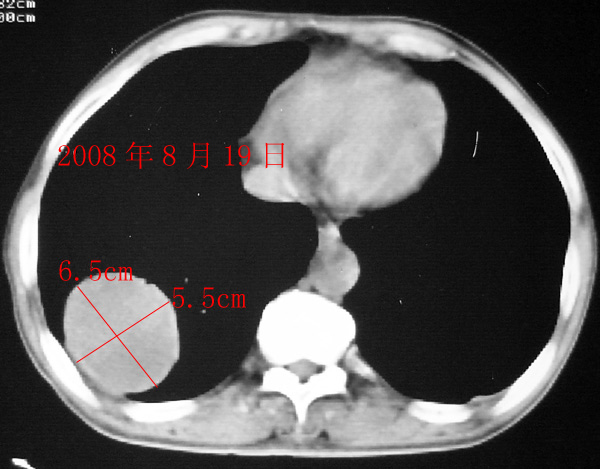

2008年8月19日ct所见为实性肿物,轻度强化,而患者仅有“胸闷、食欲不振”的症状,没有发热病史,因此考虑良性肺肿瘤可能性大。

本次ct检查,在肿块内出现了气体,而且“近期始终间断性发高烧”,考虑肿瘤合并感染可能性。